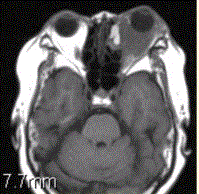

问题 患者女,64岁,左眼突出5年余。查体左眼球前突6mm,眼球运动自如,眼底无异常,下睑扪及边界不清、质软的肿块,视力正常,MR表现如下图。 经抗生素及激素治疗后好转,则诊断支持

选项 A.炎性假瘤 B.眼型Grave病 C.黑色素瘤 D.转移瘤 E.眼眶海绵状血管瘤 F.弥漫型淋巴管瘤

答案 A

解析 A